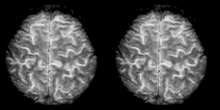

Cognitive neuroscience aims to reduce cognition to its neural basis using new technologies such as fMRI, repetitive transcranial magnetic stimulation (rTMS) and Magnetoencephalography (MEG) as well as older methods such as Positron emission tomography (PET) and Electroencephalography (EEG) studies. Due to the correlational designs used in fMRI, many scientists have coined this up and coming field as the new phrenology in the sense that techniques such as fMRI rely heavily on complex statistics.[17] Type 1 errors can lead scientists to draw premature and incorrect causal relationships if improper designs are used.[18]